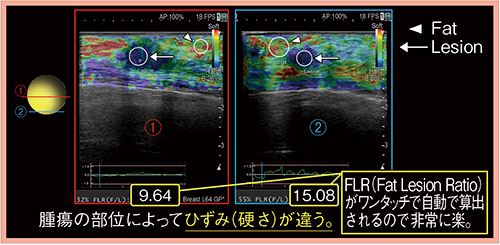

DFIでは,腫瘍中心よりも辺縁から多くの血流を受けており,部位によって観察される血流量(分布)が異なることがわかる(図1)。また,Bモードだけでも悪性と判断できるが,RTEも悪性を支持する所見であった(図2)。RTEでは,脂肪と病変のひずみの比であるFat Lesion Ratio(FLR)(図2□)がワンタッチで自動計測でき,非常に簡便である。FLRは数値が大きいほど腫瘍が硬いことを示すが,この腫瘍は中心が9.64,辺縁が15.08と部位によって硬さが異なっていた。針生検の結果も,部位によって細胞成分や線維(間質)の分布が不均一であることから,DFIやRTEの差は組織構築成分の違いを見ているものと考えられる。DFIとRTEを組み合わせることで,より的確な生検部位の同定が可能になると思われる。

図2 症例1:RTEおよびFLRの結果